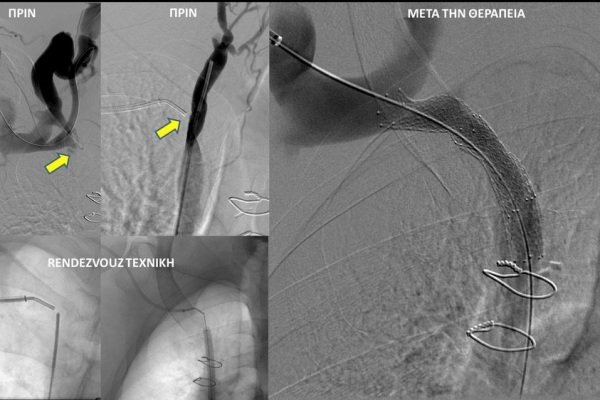

- Φιστουλογραφία ονομάζεται η αγγειογραφία των μοσχευμάτων-fistula αιμοκάθαρσης. Είναι είναι μια ελάχιστα επεμβατική διαγνωστική εξέταση που ενδείκνυται για την ανάδειξη στενώσεων που θέτουν σε κίνδυνο την λειτουργία της αγγειακής πρόσβασης και δεν επιτρέπουν την επαρκή αιμοκάθαρση. Η εξέταση διενεργείται με τη χρήση αγγειογράφου και ιωδιούχου σκιαγραφικού μέσου.

- Η φιστουλοπλαστική είναι μια ελάχιστα επεμβατική μέθοδος αντιμετώπισης της δυσλειτουργίας των αρτηριοφλεβικών προσβάσεων αιμοκάθαρσης (μοσχευμάτων ή fistula) λόγω αρτηριακών ή φλεβικών στενώσεων, χωρίς να χρειαστεί χειρουργείο. Η φιστουλοπλαστική διενεργείται σε αγγειογραφική σουίτα με συνθήκες αποστείρωσης και υπό τοπική αναισθησία, ενώ η θεραπεία περιλαμβάνει συνήθως την διαστολή της αγγειακής στένωσης με ειδικό «μπαλονάκι» υψηλών πιέσεων. Στη περιπτωση όπου οι αγγειακές διαστολές δεν επιφέρουν το επιθυμητό αποτέλεσμα, τοποθετούνται μεταλλικές ενδοπροθέσεις (stents).